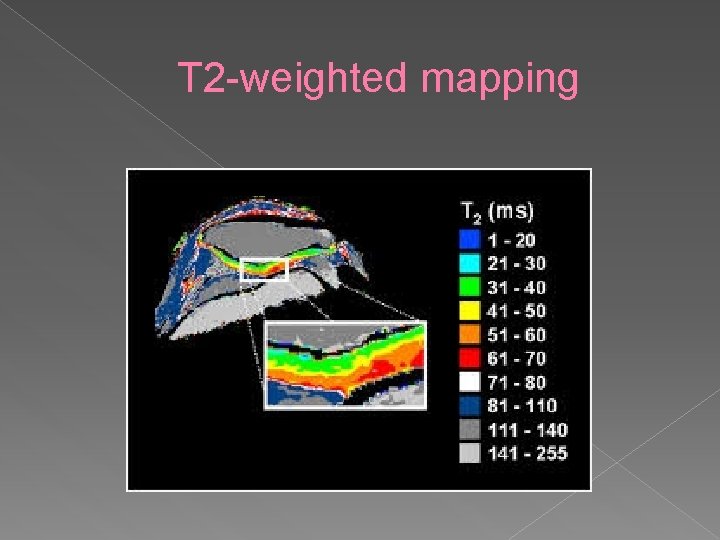

T 2 -weighted mapping Describes the composition of hylaine cartilage on basis of collagen structure and hydration • In healthy cartilage, T 2 values increase from deep to superficial • Based on anisotropy of collagen fibers running parallel to subchondral bone • T 2 values vary with age and with distance to subchondral bone •

T 2 -weighted mapping

T 2 -weighted mapping